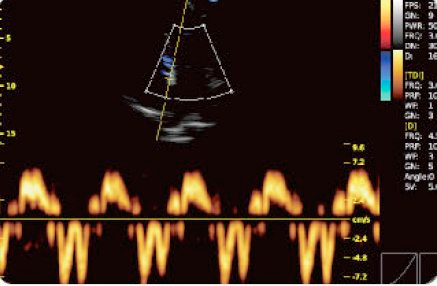

O Doppler tisular (TDI)

- TDI é uma tecnologia de ecocardiología que mede o nível direto da velocidade do miocardio ventricular esquerdo e direito.

- Acelera os processos à hora de começar a tratar com o paciente.

- As diastolicas TD refletem o estado do miocardio em repouso.